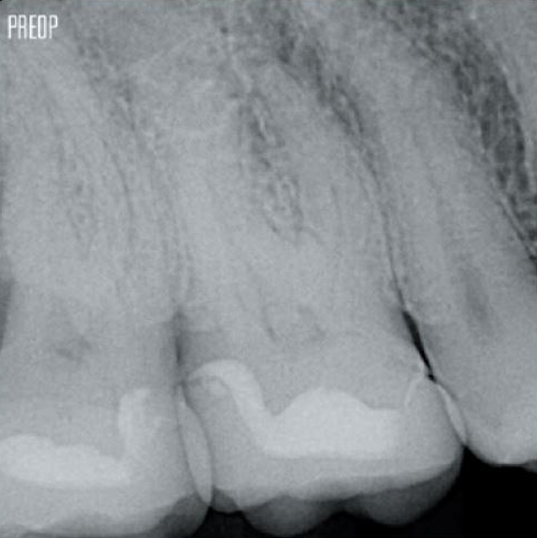

Mehr erhaltenes Dentin. Angemessene Formgebung, Spülung und Obturation gewährleistet.

Fotos mit freundlicher Genehmigung von Dr. Ahmed Salman